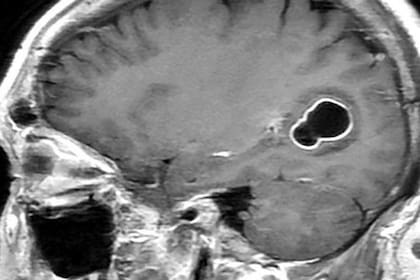

Al realizarle tomografías, los médicos encontraron la presencia de numerosos quistes en el cerebro que, según luego comprobaron con estudios posteriores, en realidad eran larvas de tenia que se habían instalado en su cerebro y que eran las causantes de una infección conocida como neurocisticercosis.

Según los Centros para el Control y la Prevención de Enfermedades (CDC, por sus siglas en inglés) de EE.UU., las larvas de tenia “entran en tejidos como los músculos y el cerebro y forman quistes. Cuando se encuentran quistes en el cerebro, la afección se llama neurocisticercosis”.